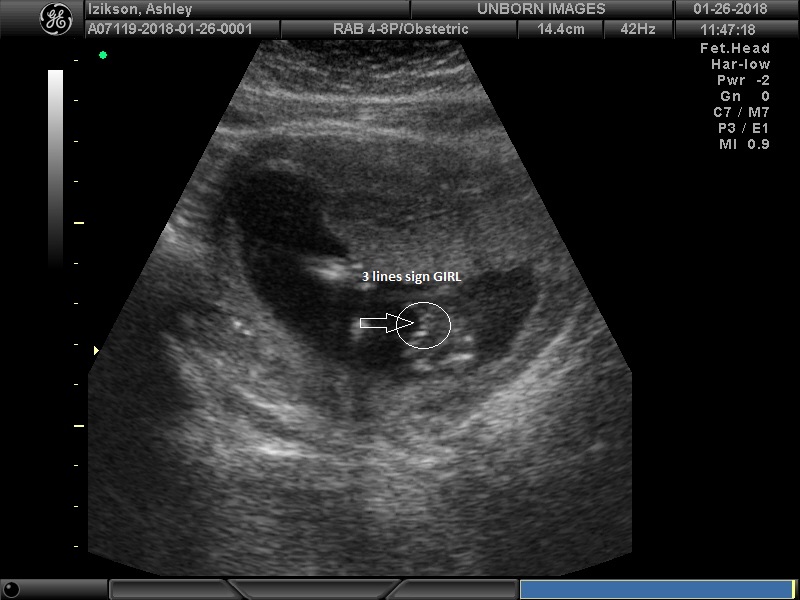

You won t be able to tell clearly until about 18 20 weeks. The gender of your baby is revealed at your second scan between 18 and 21 weeks but there s another test people use to determine if it s a boy or girl credit. The 127 is how many beats per minute your baby s heart is pumping. In a little over a week i find out.

I guess it may be different for everyone. And yes teh sex organs are all done at 15 weeks even before that. In addition to an ultrasound the sex of your baby can be confirmed with an amniocentesis or chorionic villus sampling cvs. At my second scan at 23 4 she said it looked like a girl but it looked less clear on this older scanner.

It is possible to find out the gender though the baby is very. If you have an amnio at 16 weeks you can find out by 18 weeks.